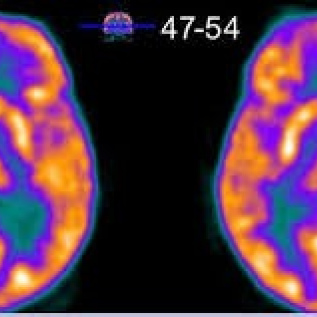

Gamagrafia metabolica cerebral con 18 FDG (PET-CT). 920106 Idime (2024)

IDIME. Instituto de Diagnóstico Médico. Código de Convenio : 8915

INCLUYE UNIDOSIS FDG-18